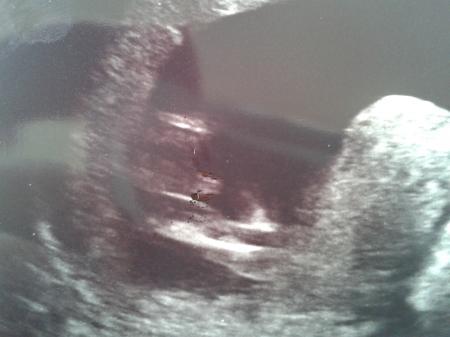

soind meines erachtens nach die oberschenkel dazwischen das würde ich behaupten sieht aus wie die hoden zeige dir mal mein outing bild

Bild zu

Das ist ja ein tolle Bild. Da erkenne sogar ich die gesuchten Körperteile ;o) Nur an unserem Bild kann ich das weiterhin nicht erkennen :o( LG